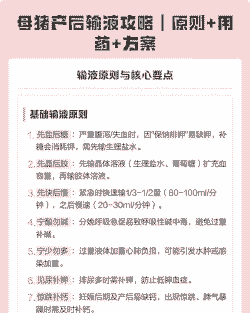

母猪产后输液的次数主要根据具体情况而定,但一般 至少一次。以下是一些具体的建议:

一般情况

母猪在产程后期就可以开始输液,通常一次即可。输液配方可以包括生理盐水、葡萄糖、头孢等,具体药物和配方可以根据自家猪的情况进行调整。

需要多次输液的情况

对于助产母猪和生病母猪,可能需要增加1-2次输液。

如果产程超过4个小时,或者母猪在分娩过程中出现异常情况,可能需要注射2-3次甚至更多次。

具体输液内容

产后静脉输液一般采用生理盐水、青链霉素、鱼腥草、复合维生素B、缩宫素等药物组合,同时加入葡萄糖溶液、维生素C、黄芪多糖等,以快速补充体液损失,帮助母猪恢复体力。

某些情况下,还会使用宫炎净、林可霉素等药物进行子宫灌注。

抗生素使用

产后使用抗生素时,短效抗生素如青霉素每天至少两针,长效抗生素如长效土霉素、林肯霉素每天至少一针。具体使用剂量和频率可以根据母猪的实际情况和兽医的建议进行调整。

建议

根据具体情况制定输液计划:不同的母猪和不同的生产情况需要不同的输液方案,建议根据母猪的具体情况和兽医的建议来制定个性化的输液计划。

注意药物选择和搭配:选择合适的药物和合理的搭配,以确保治疗效果的同时减少药物副作用。

观察母猪反应:在输液过程中,要密切观察母猪的反应和恢复情况,及时调整治疗方案。

希望这些信息能帮助你更好地了解母猪产后输液的相关知识。